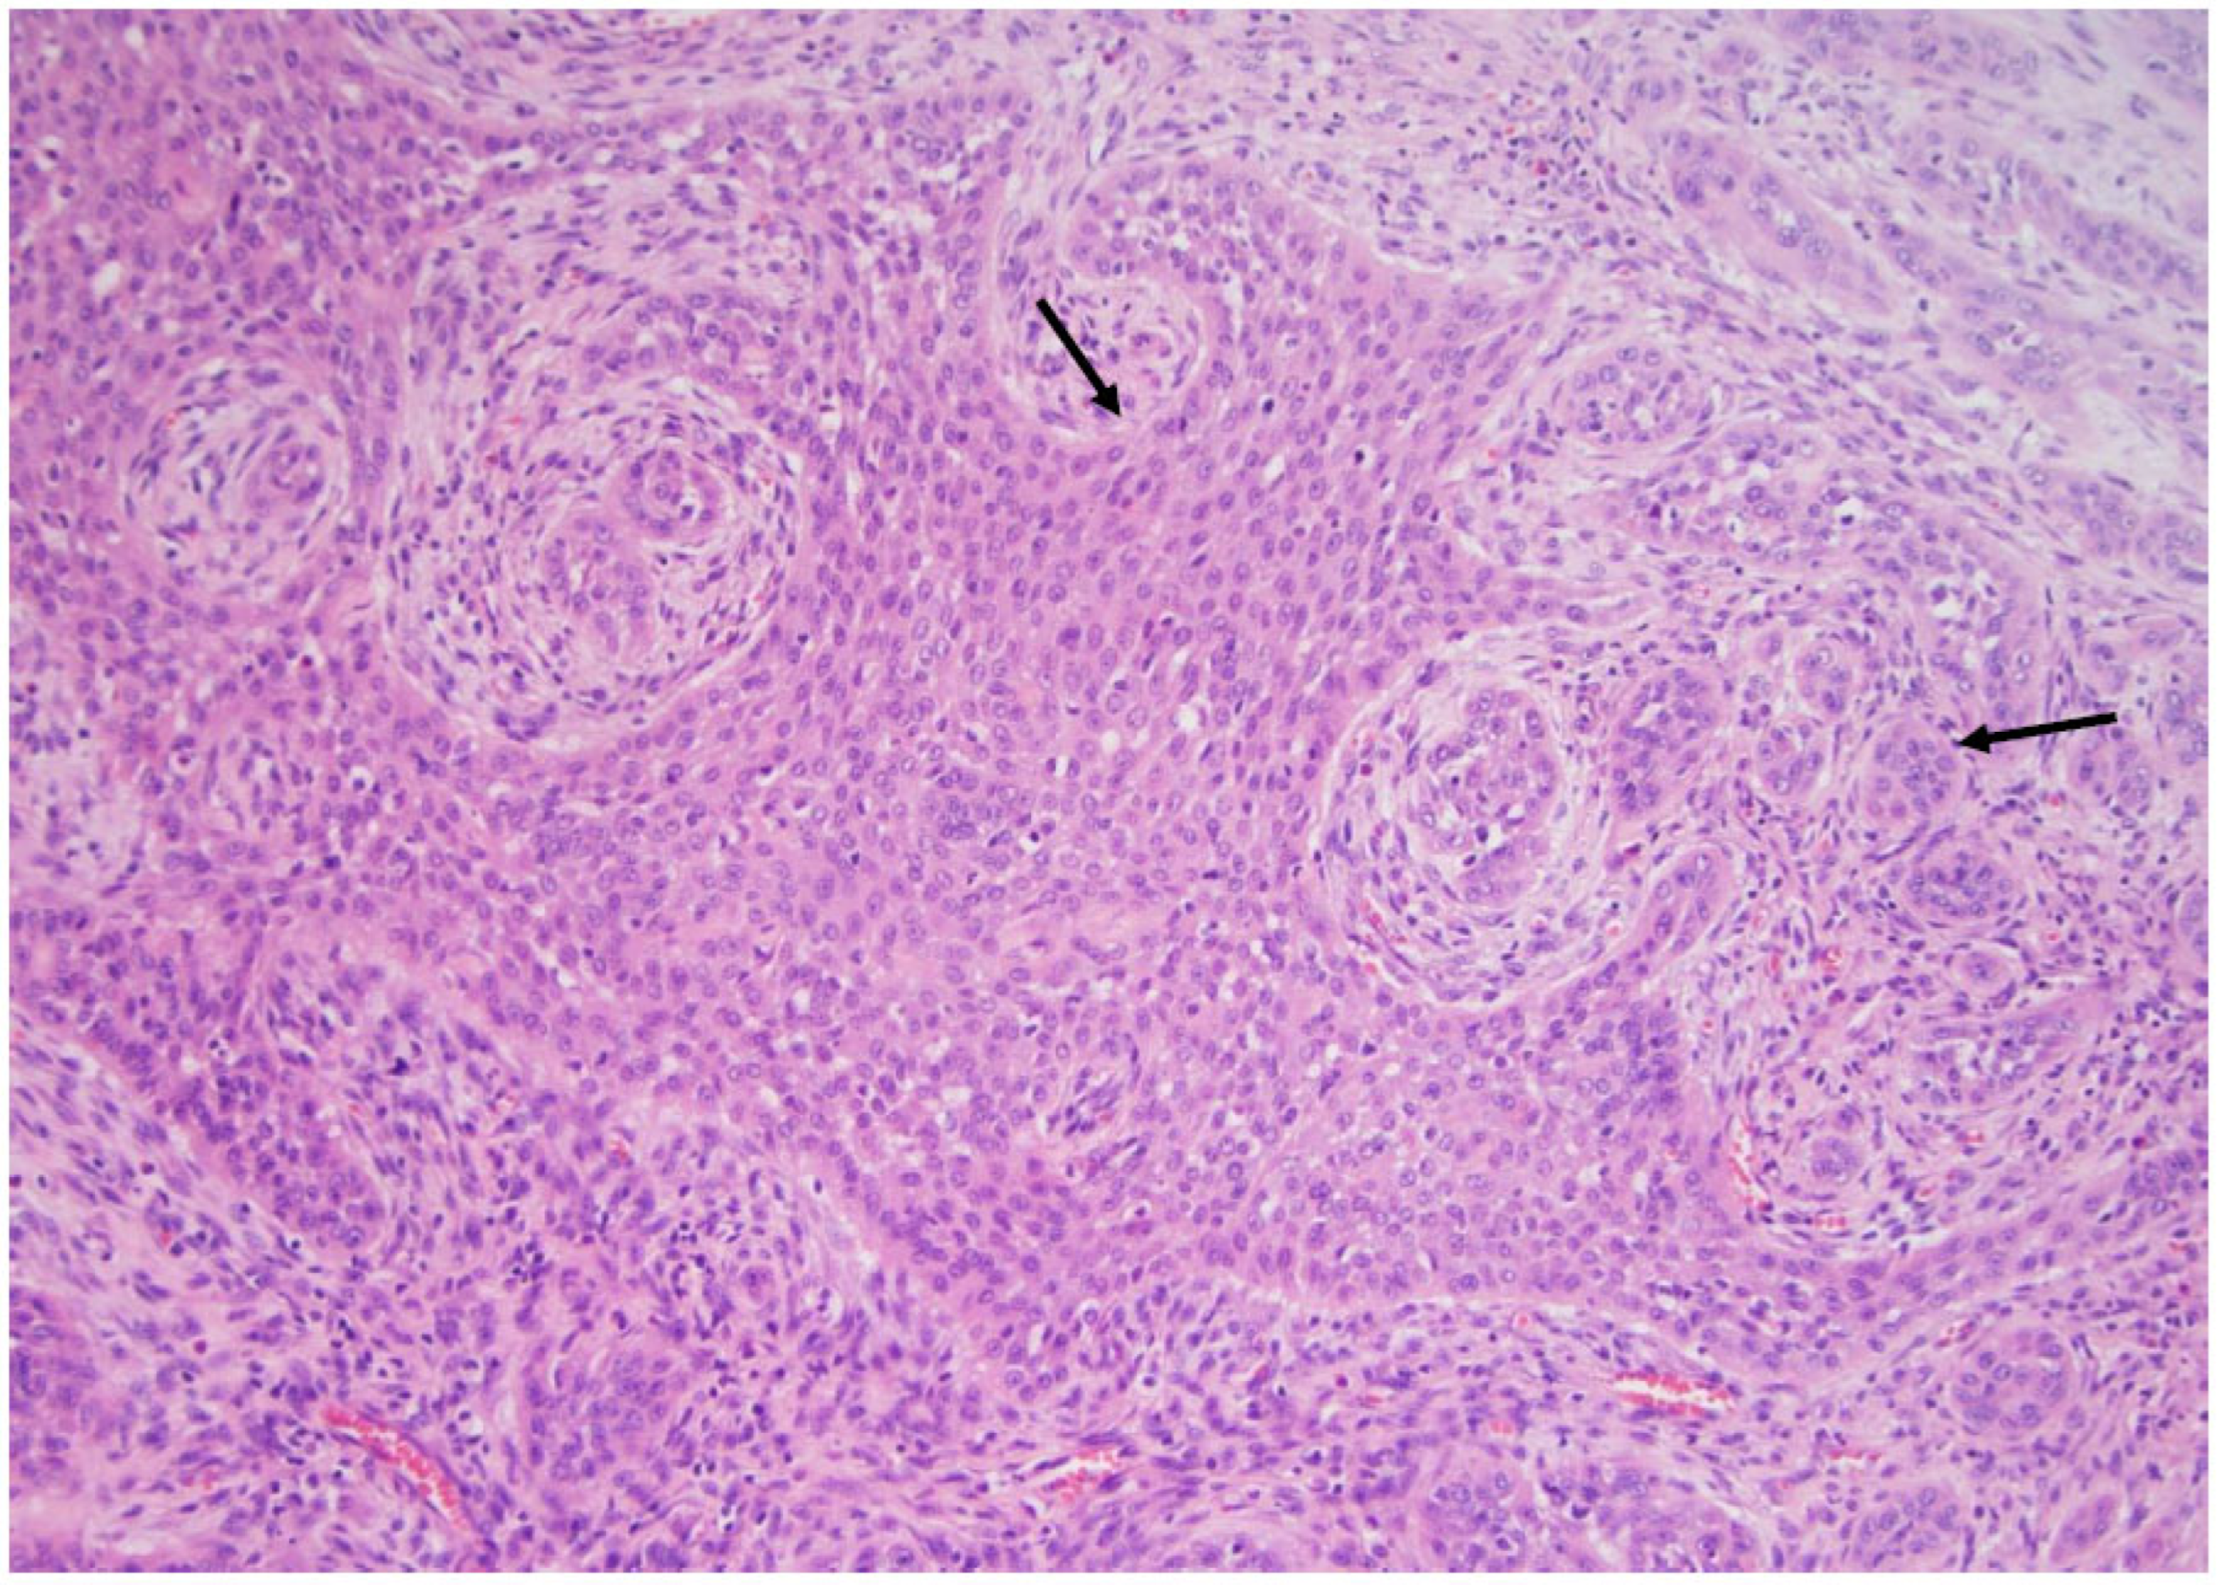

Figure 8. Squamous cell carcinoma is characterized by sheets and ribbons (arrows) of cohesive cells with variable degrees of differentiation, (×200, H&E stain).

The diagnostic morphological criteria for this carcinoma did not change from 2017 to 2022. It is a very rare yet highly aggressive cancer (Figure 7). Nevertheless, it is now recommended these carcinomas be promptly tested for the BRAF V600E mutation since the efficacy of the targeted therapies has been proven, even for anaplastic carcinoma. Moreover, the very rare squamous cell carcinoma (Figure 8), pure or associated with another type of carcinoma, should be regarded as the equivalent of an anaplastic component and managed accordingly.